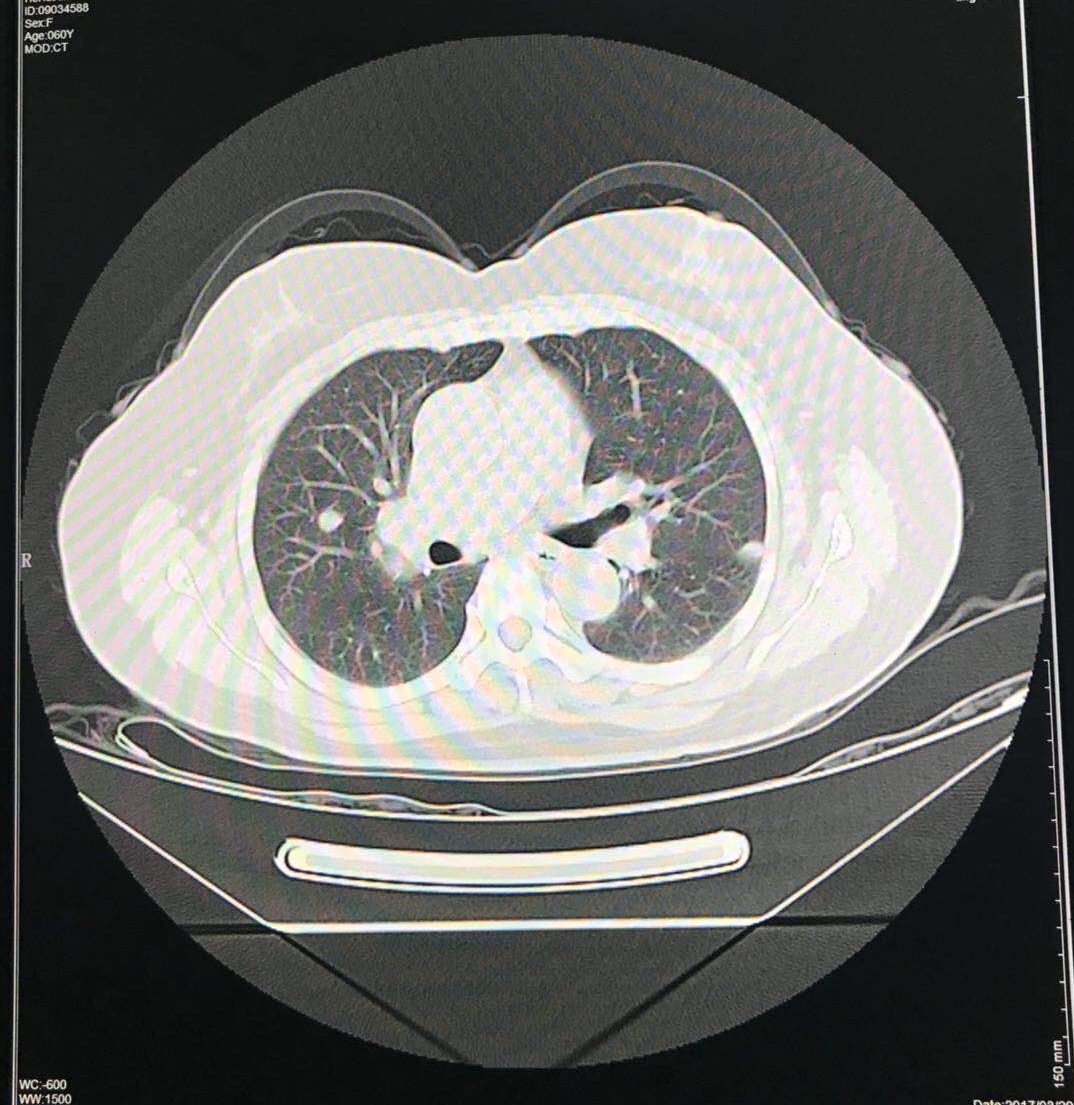

颈胸部CT:双侧胸锁乳突肌深面及后缘、双侧锁骨上窝、纵隔及双肺门多发肿大淋巴结,部分似融合成团状,颈部较大者3.2×2.1cm,纵隔较大3.2×2.3cm,首先考虑淋巴瘤,未排转移,双肺多发大小不一结节,点片状,条索网格状密度增高,较大者位于左肺上叶舌段径线2.0×1.7cm,性质待定。右颈动脉鞘间歇多发积气影伴相应脂肪间隙模糊不清。

2017-3-20:查CA 125 339U/ml,收住入院。CT:卵巢癌术后改变,左锁骨上、纵膈肺门及腹膜后多发淋巴结肿大,较前明显增多增大,较大约3.5×3.5cm。两肺新见多发转移瘤,大约1.3×1.4cm。